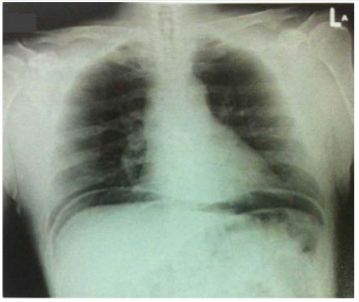

9. 某位病人最近一周心窩處 (epigastric region) 常感悶痛,今天因疼痛突然加劇而被送至急診室。身體診察發現上腹部肌肉緊繃 (rigid),觸診時感到相當硬;站立胸部X光照相結果如圖示。下列各項臨床診斷,何者最可能? (A) Reflux esophagitis (B) Mallory-Weiss tear (C) Acute cholecystitis (D) Perforated peptic ulcer (E) Myocardial infarction